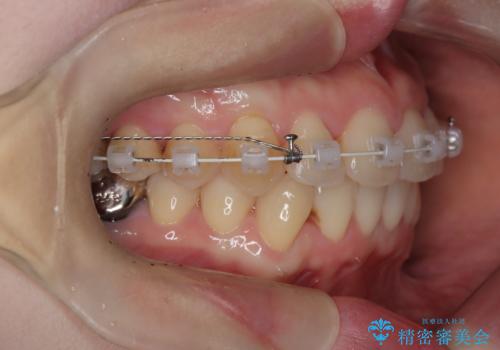

- 前歯の翼状捻転の改善を希望してこられた患者様です。

下顎の叢生はインビザラインで解決することがきましたが、上顎の捻転が完全には改善できなかったため、上顎は途中からワイヤーを用いて治療を行っています。

捻転の改善はインビザラインで苦手とするところですので、うまく治らない場合はワイヤーを提案しています。